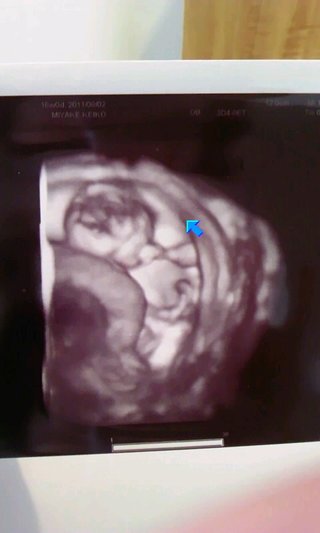

エコー写真…浮腫(;_;) 投稿画像

エコー写真…浮腫(;_;)